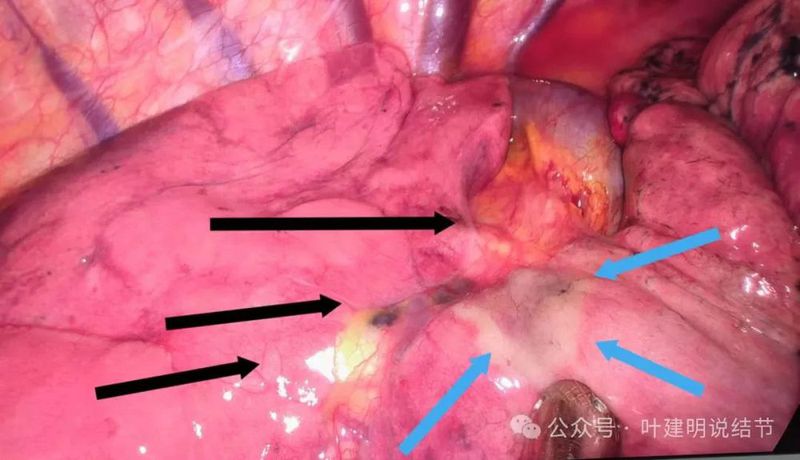

镜下见病灶2贴着叶间裂侧的胸膜,略显灰白,但没有影响下叶。上图黑色箭头示叶间裂;蓝色箭头示肿瘤。

标本表面观见病灶贴着胸膜,但支气管断端距其仍有一定距离的。